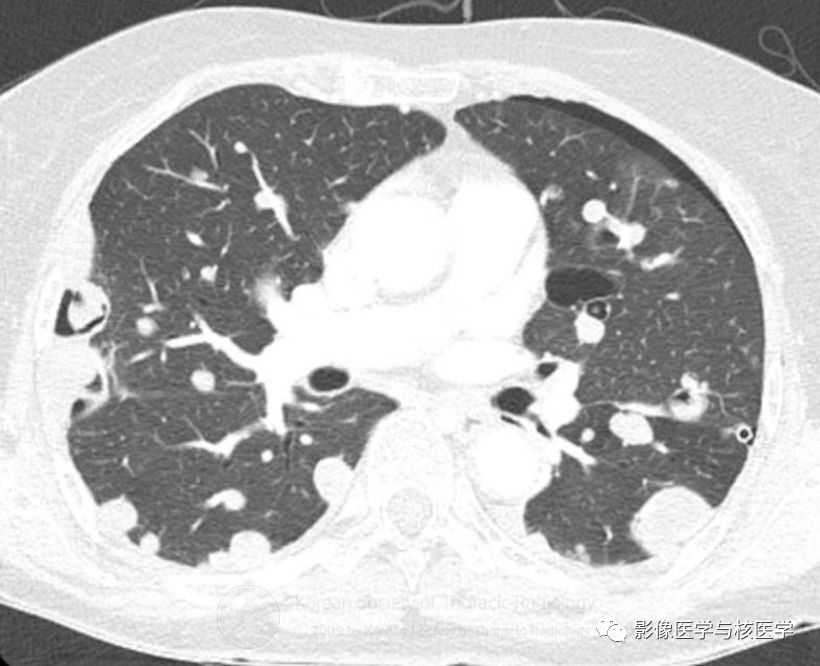

图3 胸部CT肺窗

Figure 2-4. On chest CT after chest tube insertion in left hemithorax, there are multiple nodules and masses with/without cavity in both lungs.

图2-4.胸部CT显示左侧气胸置管后,两肺多发结节或肿块伴或不伴空洞。